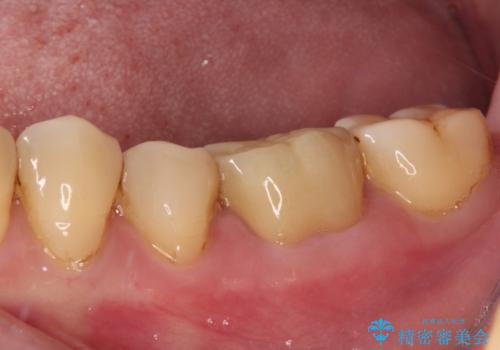

フルジルコニアクラウンは、やや光沢のある材質ですが、奥歯に装着した場合にはさほど気にならず、自然な口元の印象となりました。